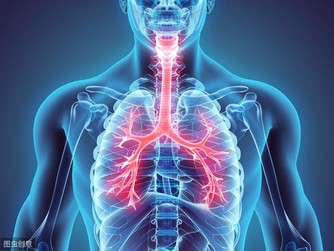

濕氣,一年四季都有。尤其在夏天,比較盛行,加上夏天氣候熱,濕氣遇熱就變成了濕熱。